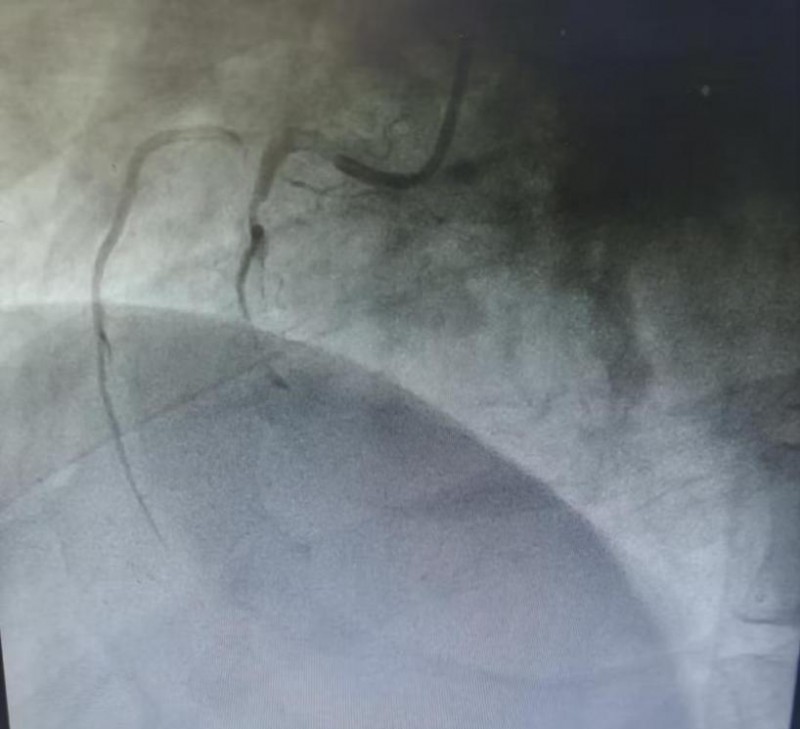

复查心电图明确诊断为急性下壁心肌梗死,病情极其凶险。冠脉造影结果显示:冠脉三支严重病变,其中右冠状动脉中段急性完全闭塞,伴大量血栓影,合并右冠自发性夹层,属于极高危复杂病变,随时可能再次发生恶性心律失常、心源性休克甚至猝死。

(术前冠脉造影)